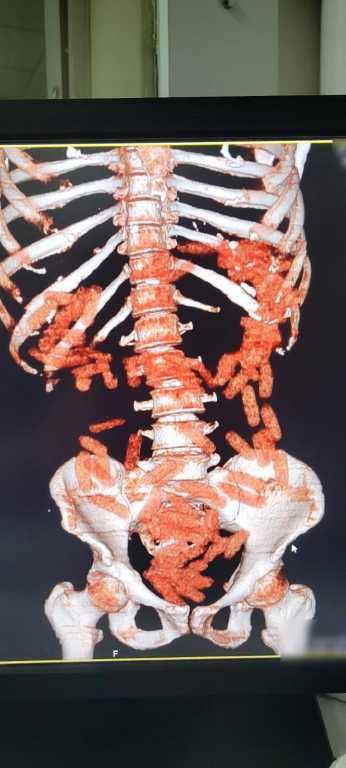

Gözaltına alınan A.G.'nin röntgen ve tomografi görüntülerinde midesinde uyuşturucu bulunduğu belirlendi. Gerçekleştirilen ameliyat sonucunda, şüphelinin midesinden 88 kapsül halinde toplam 974,52 gram afyon sakızı çıkarıldı. A.G., taburcu edildikten sonra her iki şüpheli "uyuşturucu madde ticareti" suçlamasıyla mahkemeye sevk edilerek tutuklandı.